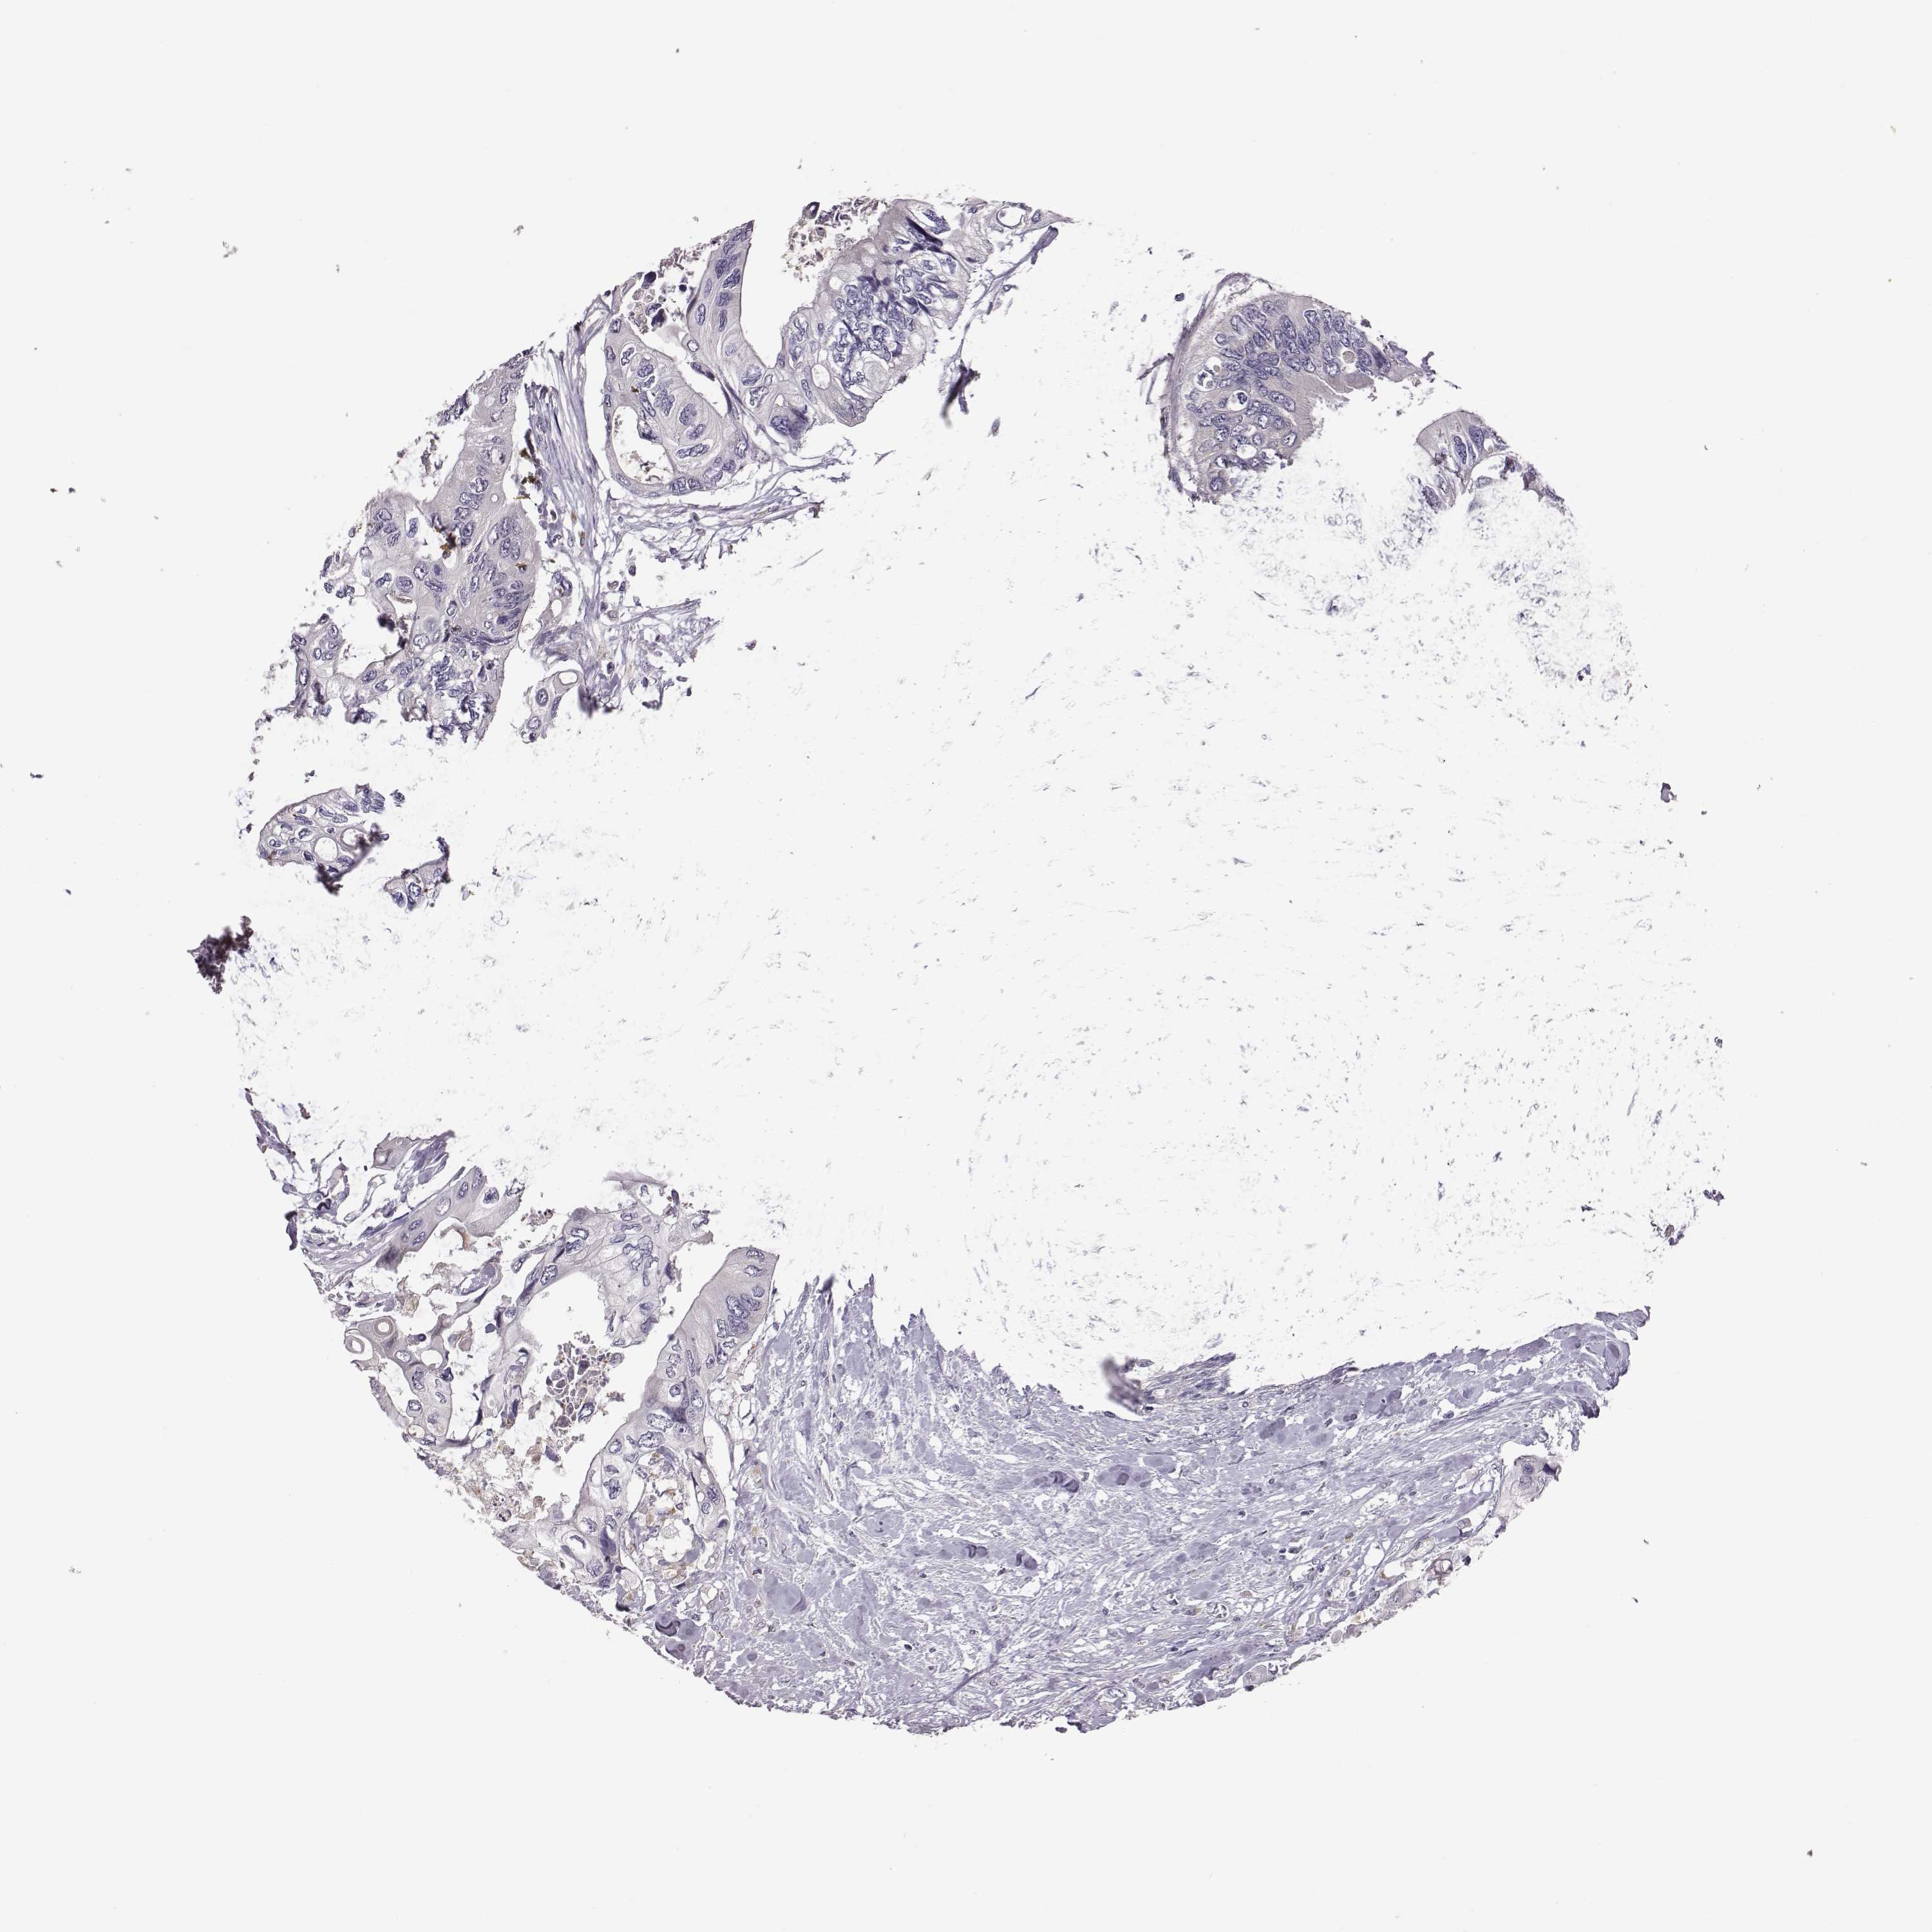

CANCER COLORECTAL CANCER Show tissue menu

Colorectal cancer

Human cancer